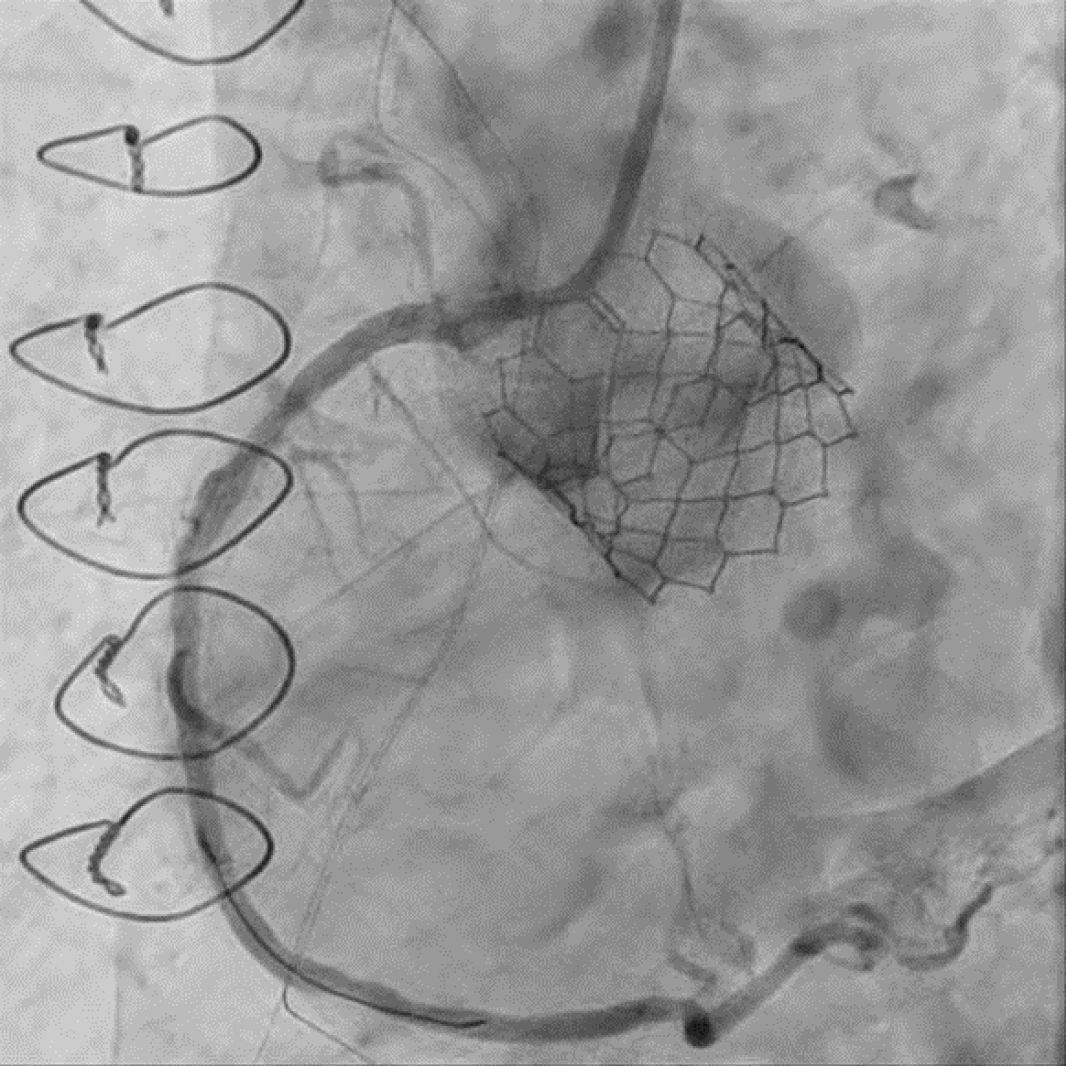

84세 남자가 아침 식사 후부터 시작된 오목 가슴 통증이 있어 응급실에 방문하였다. 과거력상 당뇨병, 고혈압이 있었고 15년전 관상동맥우회술 (coronary artery bypass graft, CABG, LIMA to LAD, Y-graft to Diagonal and Obtuse marginal branch, vein graft to PDA branch)을 시행 받았다. 또한, 1개월전 본원에서 심한 대동맥판막 협착증으로 경피적 대동맥판막 삽입술 (TAVR, Sapien 3 Ultra 26mm)을 시행 받았다. 당시 촬영한 관상동맥조영술상 LIMA graft는 잘 유지되고 있었지만 Y-graft 및 vein graft는 완전히 막혀 있는 상황이었다. 혈압 120/80 mmHg, 심박수 110회/분, 호흡수 20회/분, 체온 36.1℃, 산소포화도 98%였다. 응급실 방문 후 5분째 검사한 심전도에서 inferior leads (II, III, aVF)에 ST elevation이 있어 acute inferior ST-elevation MI로 진단하였다. 응급 관상동맥조영술상 우관상동맥 개구부 및 중위부의 심한 협착(그림 1) 이 있어 우관상동맥에 약물용출스텐트 2개를 삽입하는 일차적 관상동맥중재술(그림 2)을 시행하였다.